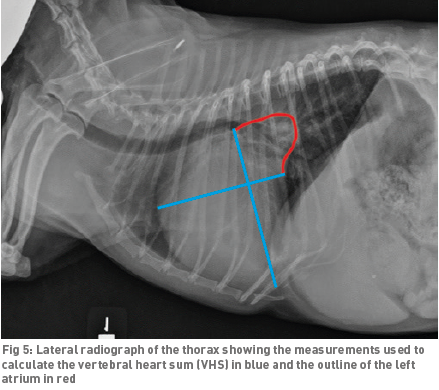

Vertebral Scale System to Measure Canine Heart Size in Radiographs. James Buchanan and Jorg Bücheler. JAVMA January 1995; 206(2): 194-199. Quote: "A method for measuring canine heart size in radiographs was developed on the basis that there is a good correlation between heart size and body length regardless of the conformation of the thorax. The lengths of the long and short axes of the heart of 100 clinically normal dogs were determined with calipers, and the dimensions were scaled against the length of vertebrae dorsal to the heart beginning with T4. The sum of the long and short axes of the heart expressed as vertebral heart size was 9.7 +/- 0.5 vertebrae. The differences between dogs with a wide or deep thorax, males and females, and right or left lateral recumbency were not significant. The caudal vena cava was 0.75 vertebrae +/- 0.13 in comparison to the length of the vertebra over the tracheal bifurcation. ... The major uses of the VHS method are in helping determine whether cardiomegaly exists in dogs with minimal radiographic changes and quantification of the progression of cardiomegaly over time in a glven dog."